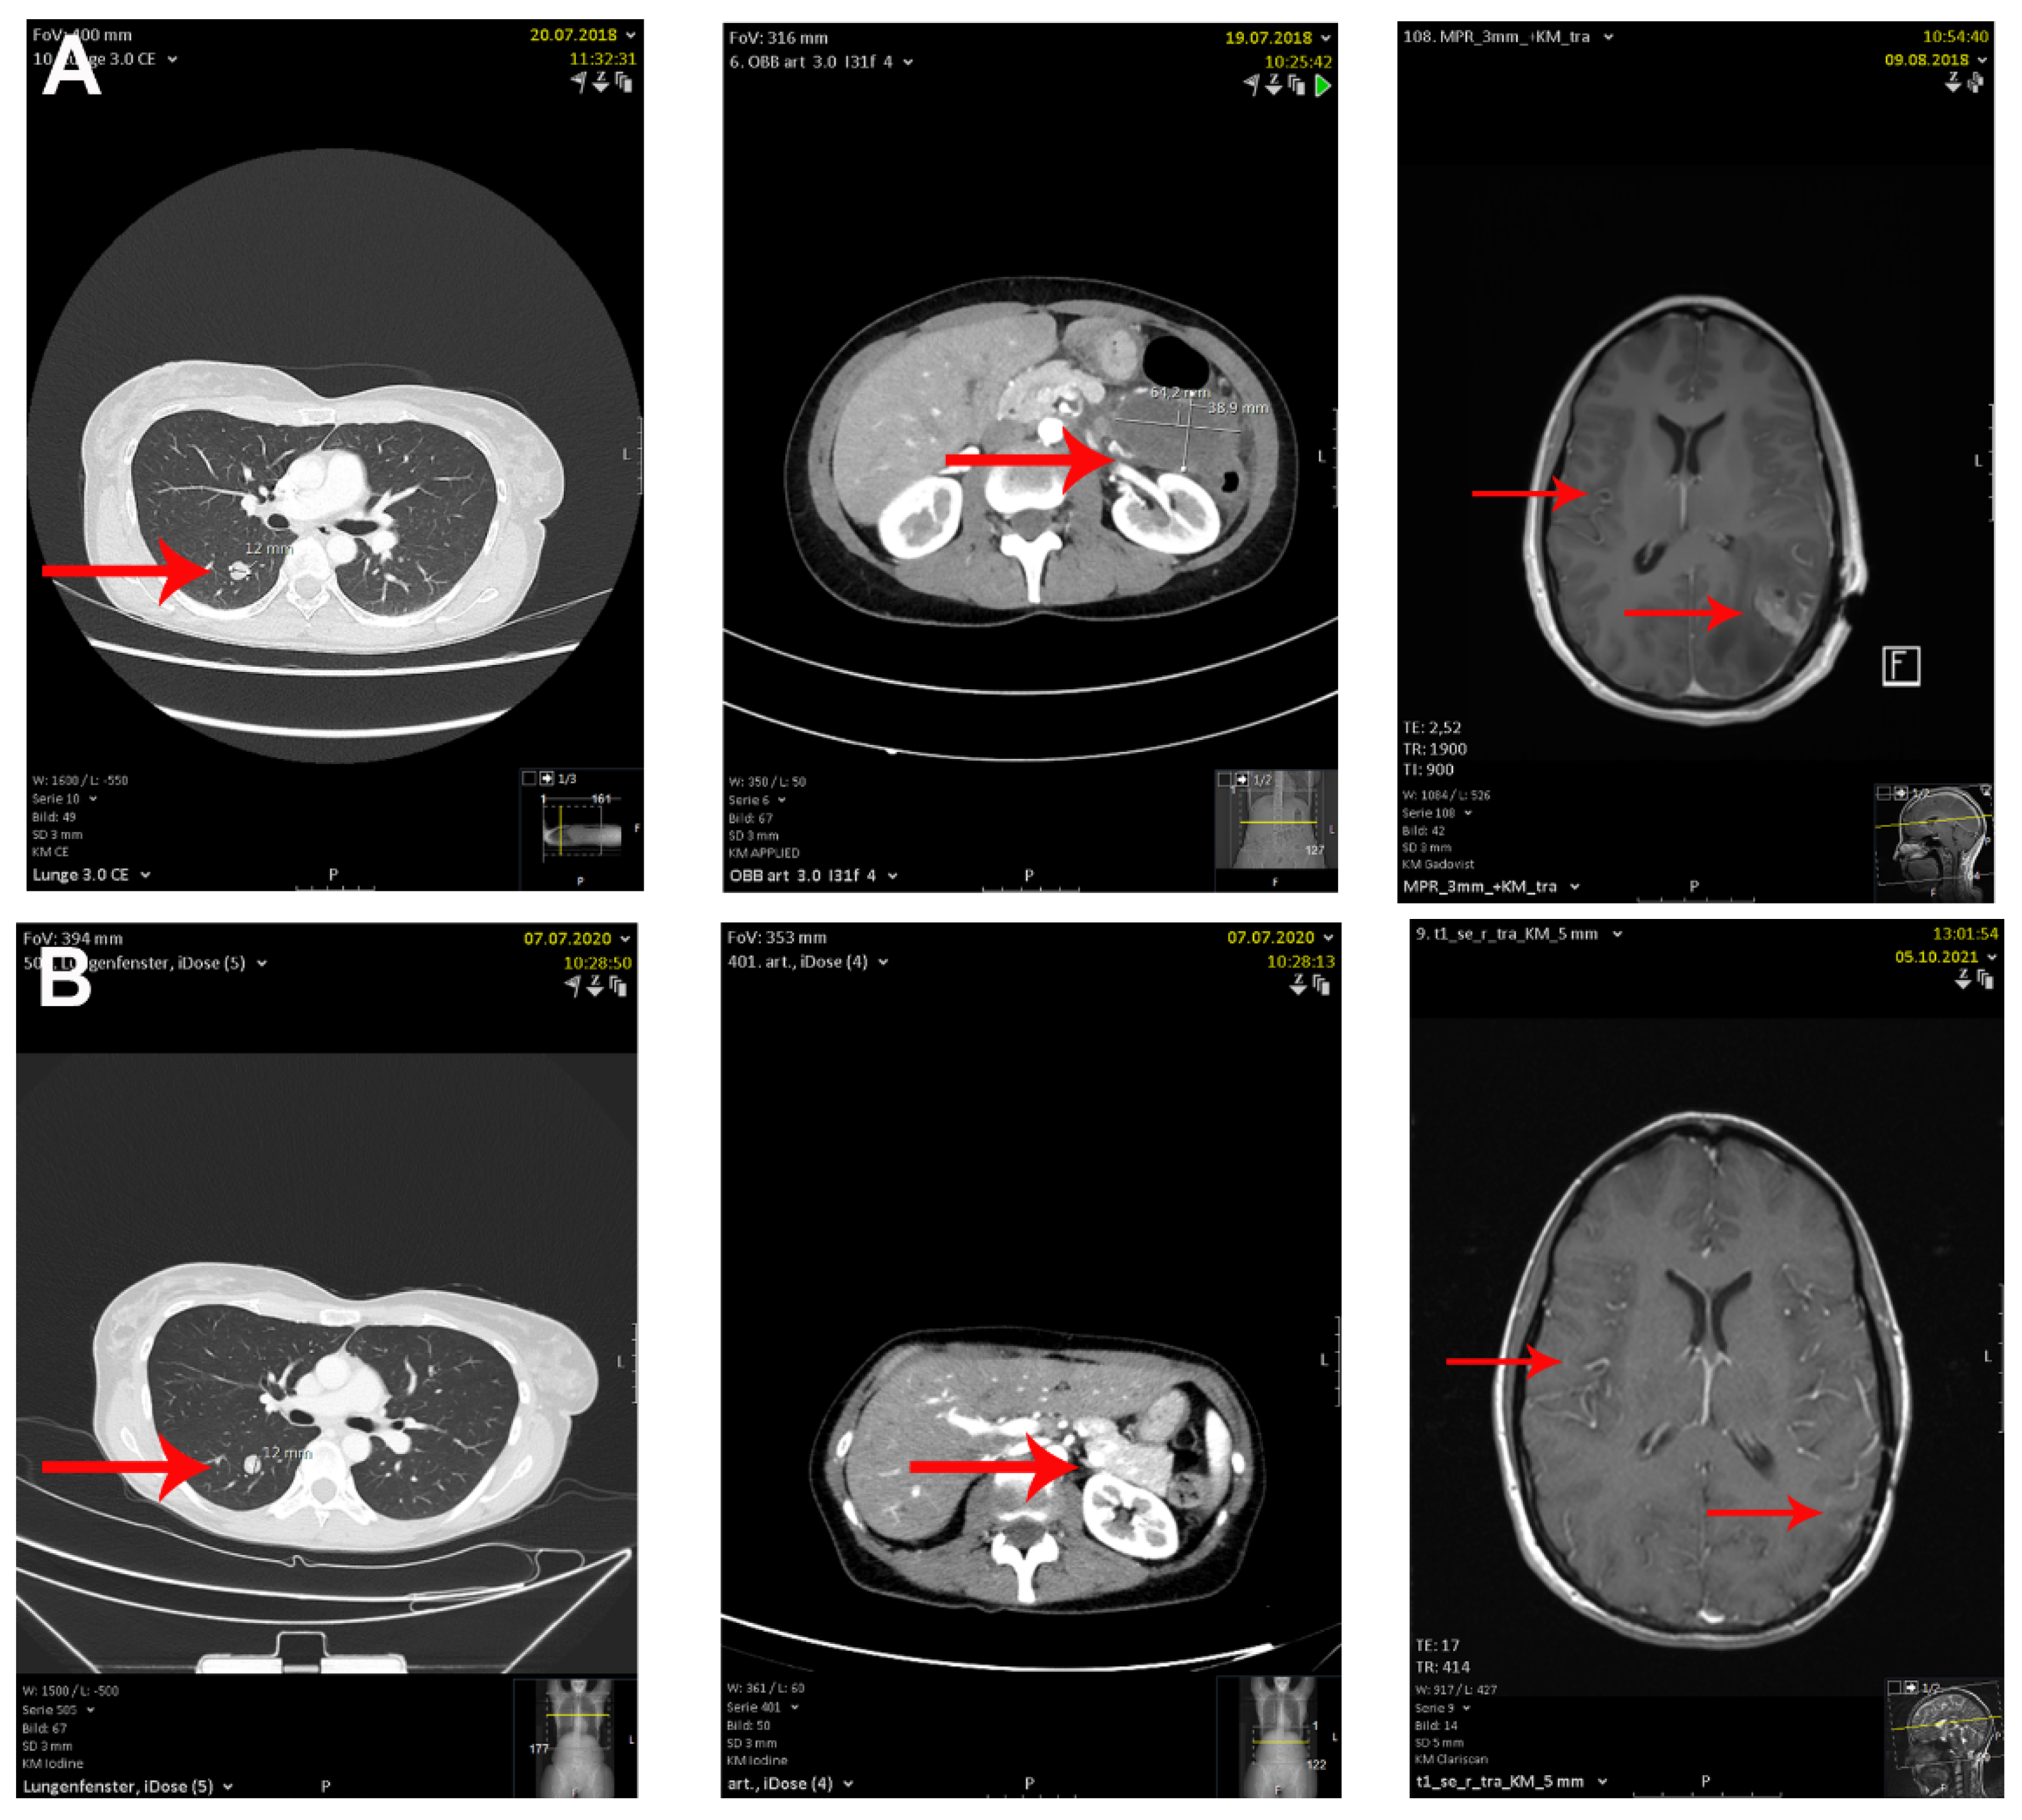

2. Case Description

| Haist et al. | unknown and upper back | 48 years and 53 years | IV | Ipilimumab + Nivolumab | After 2 and 3 cycles of cICB | complete response | hypothyroidism, vitiligo, hepatitis and colitis |